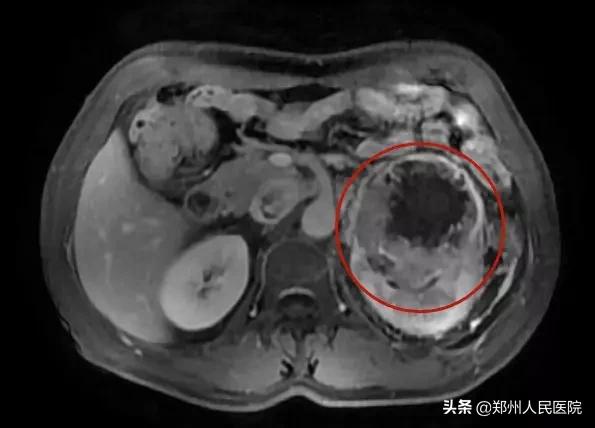

之后老王又因左腰部胀痛不适,在当地医院经过CT检查,发现左肾恶性肿瘤,建议手术治疗。

入院后,老王迅速完善相关检查,经检查最终被确诊为左肾恶性肿瘤伴下腔静脉癌栓形成。

癌栓通俗的说,就是肿瘤转移到了下腔静脉内,相当于肿瘤顺着血管长到了下腔静脉!如果癌细胞顺着静脉往心室跑,就会在静脉里形成肿瘤的团块,那就是癌栓。